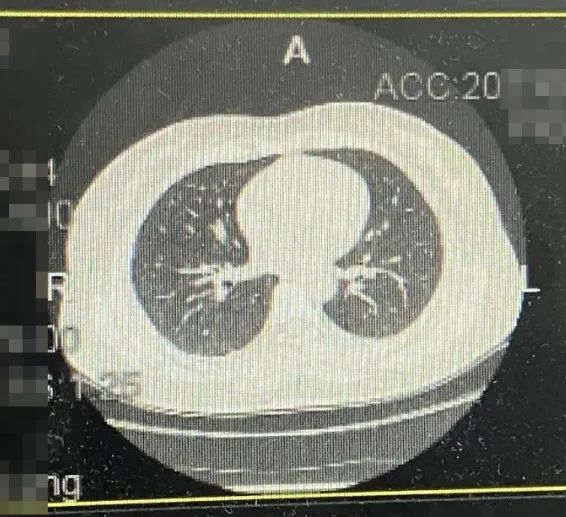

·乳腺彩超

1、右乳9点见一个低回声区,大小约0.53*0.63cm,呈直立生长,边缘成角、毛刺,内部回声不均匀,肿块内未见强回声,BIRADS 5类;

2、右乳10点见一个低回声区,大小约1.4*0.9cm,边缘成角、毛刺,内部回声不均匀,肿块内未见强回声,BIRADS 5类。

图1乳腺彩超结果